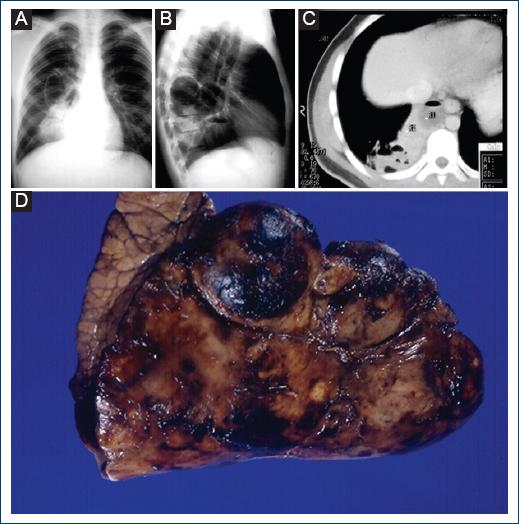

Regarding radiological studies, a cystic image was observed, of approximately 6 cm in diameter in the right hilar region, heterogeneous opacity of defined edges with some cystic areas, triangular going from the right hilum to the diaphragm with a negative silhouette. The right lateral radiograph shows a radiolucent image with defined edges occupying the posterior region, showing a hydroaeric level in one of the cystic images. The tomographic section shows a well-circumscribed posterior image on the right side, more or less homogeneous with some radiolucent areas, and some cystic images. No vessels within the images or abnormal vessels were observed with the contrast medium.

Clinical and radiological data were presented, and the right lower lobectomy was performed without any surgical contraindications, which was carried out without problems. The presence of cysts with purulent sputum was confirmed, with bronchiolar lung tissue and dilated alveoli, lined with ciliated pseudostratified columnar epithelia, and no malignancy data. The other lung tissues had a normal structure. However, it was decided, due to the patient’s age, good previous lung function, and integrity of the remaining parenchyma, to perform the lobectomy (Fig. 1).

Figure 1 A: chest X-ray with a cystic image of 6 cm in diameter and heterogeneous opacity of defined edges with cystic zones, going from the hilum to the diaphragm with negative silhouette sign. B: radiolucent image with defined edges in the posterior region and hydroaeric level. C: computed tomography scan shows a posterior circumscribed image on the right side with radiolucent areas and cystic images. D: resected lung lobe, where multiple cystic images of different sizes are observed.